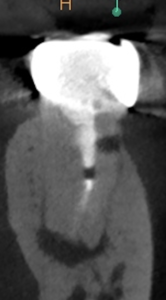

術後にPA, CBCTを撮影した。

MB

ML

DB

DL

B

問題はないだろう。

次回は半年後である。